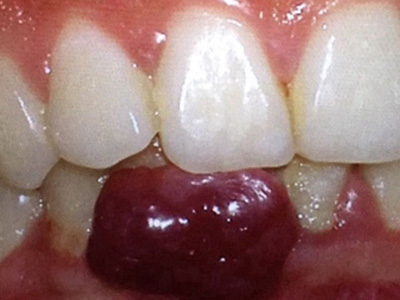

牙龈瘤是指发生在龈乳头部位的炎症反应性瘤样增生物,好发于女性,前磨牙区最为常见。牙龈瘤来源于牙周膜及牙龈的结缔组织,因其无肿瘤的生物学特征和结构,故非真性肿瘤,但切除后易复发,因此切除务必彻底,必要时拔除相关牙齿。

牙龈瘤多发于女性,以青年及中年人为常见,多发生于牙龈乳头部,位于唇、颊侧者较舌、腭侧者多,最常见的部位是前磨牙区。肿块较局限,呈圆形或椭圆形,有时呈分叶状,大小不一,直径由几毫米至数厘米。

肿块有的有蒂,如息肉状;有的无蒂,基底宽广,生长较慢,但在女性妊娠期间可能迅速增大。较大的肿块可以遮盖一部分牙及牙槽突,表面可见牙压痕,易被咬伤而发生溃疡,伴发感染。随着肿块的增长,牙槽骨壁逐渐被破坏,牙可能发生松动、移位。